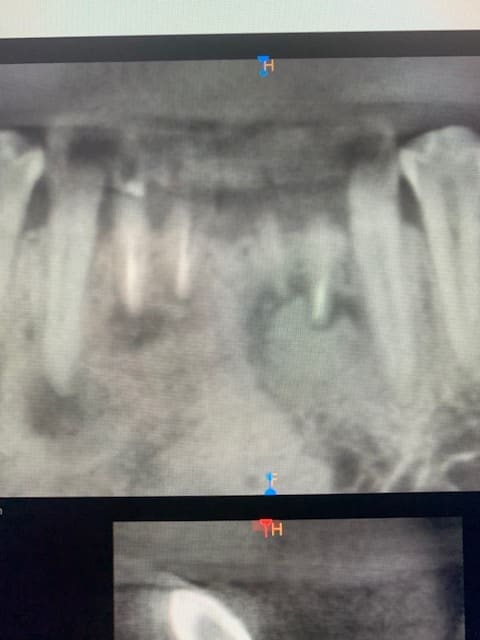

42 traitée endodontiquement a également une image apicale radioclaire. 31 probablement.

AMHA Ca ressemble beaucoup à une dysplasie cemento-osseuse.

Ça serait une dysplasie cémento osseuse apicale, dysplasie qui concerne le secteur antérieur mandibulaire.

Pour la 42 le diagnostic différenciel avec une lésion d’origine endodontique sera bien difficile à faire dans ce contexte…

Effectivement ça pourrait ressembler à une dysplasie osseuse floride :

Dysplasie cémento osseuse apicale ici car ça concerne le secteur antérieur mandibulaire.